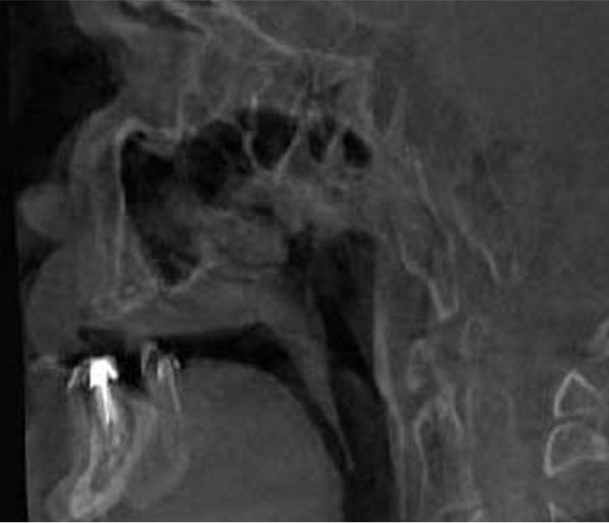

40 / 46

40) Identify the artifacts indicated by the white arrows? (1 mark)